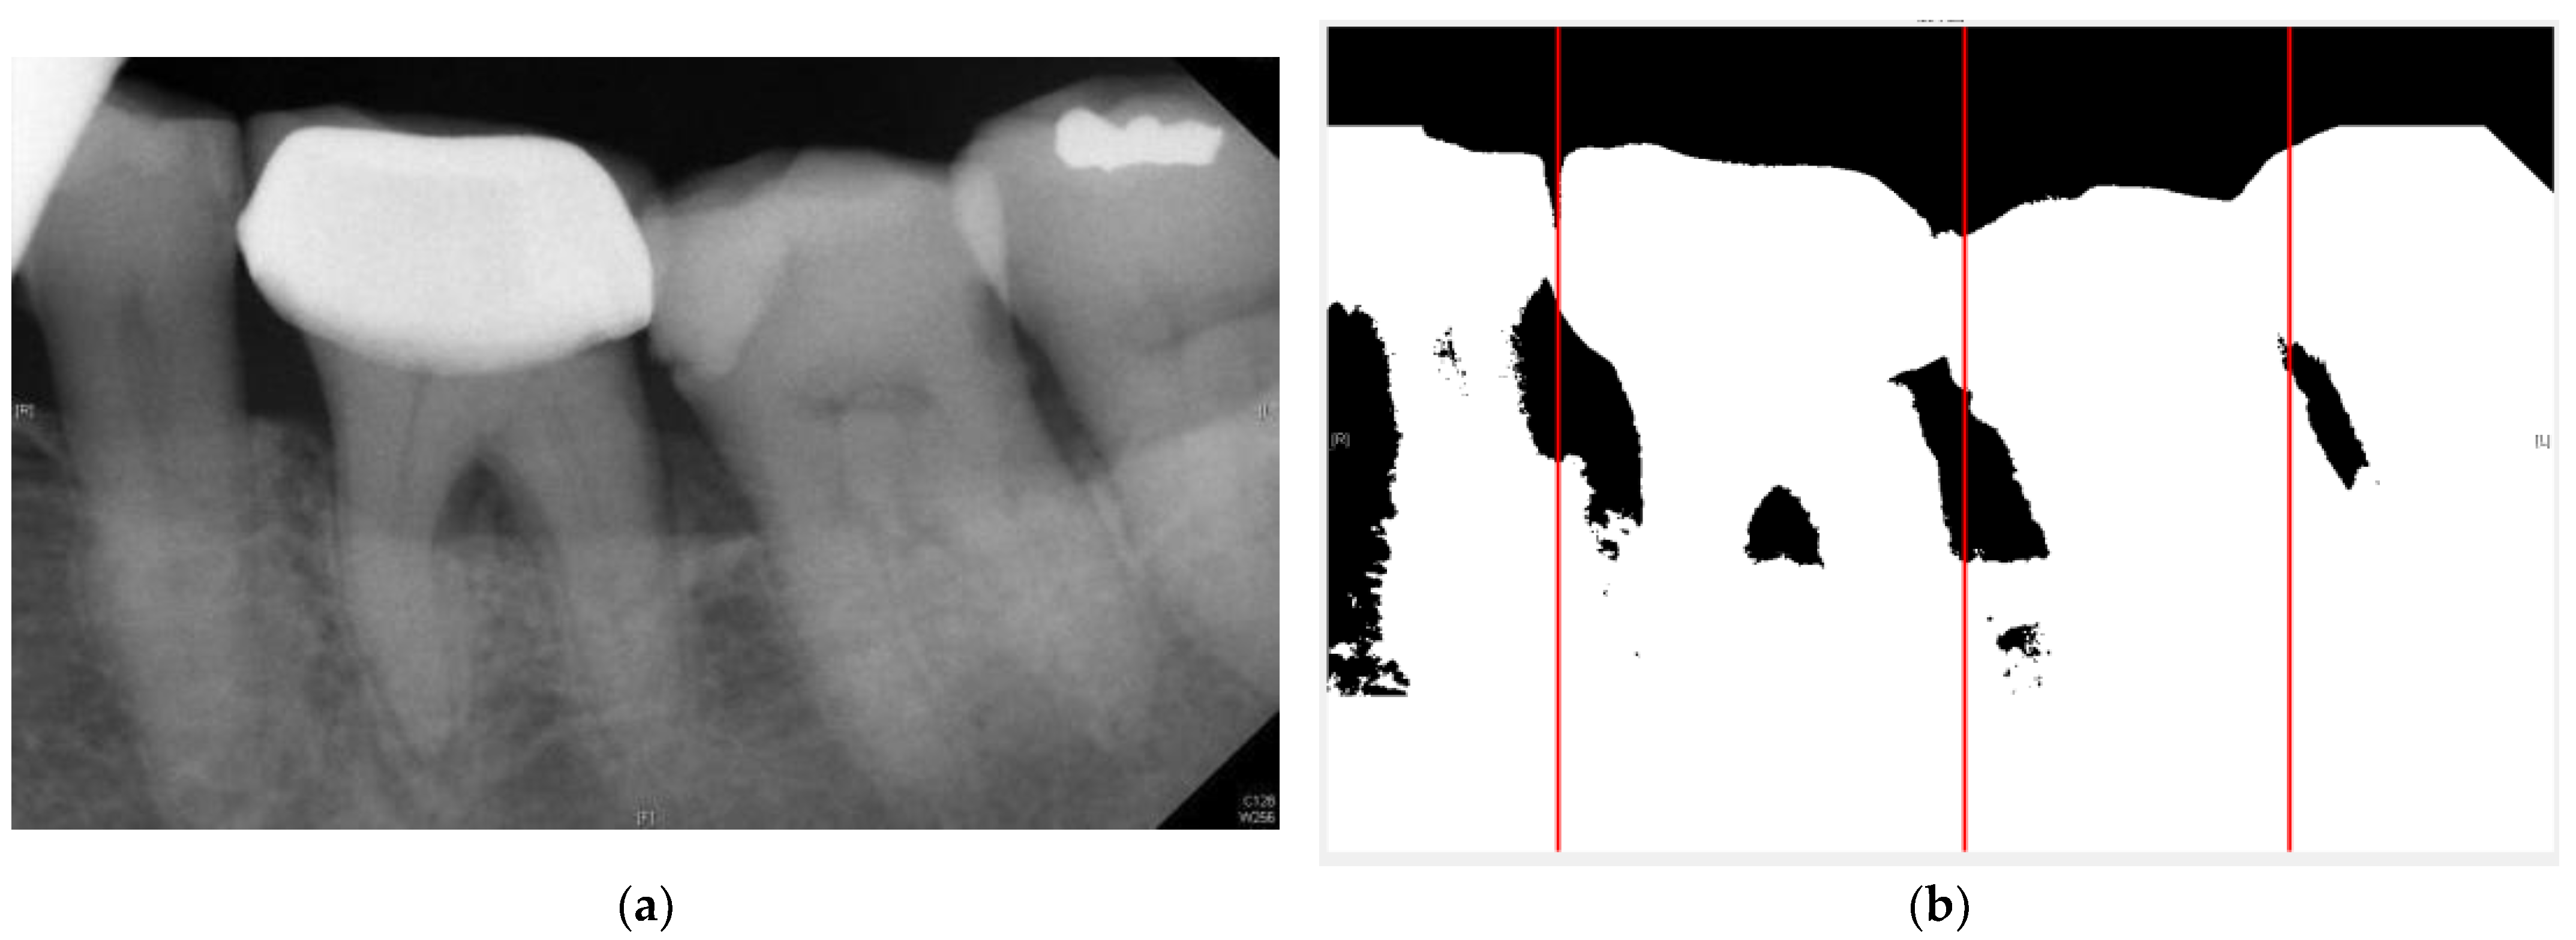

| Original Images | Gaussian High-Pass Filter | Gaussian High-Pass Filter + Mask | |

|---|---|---|---|

| Validation Accuracy | 84.16% | 87.21% | 94.97% |

| Validation Loss | 0.7634 | 0.4578 | 0.1822 |

| Model | GoogLeNet | GoogLeNet | GoogLeNet |

| Image | ![]() | ![]() | ![]() |